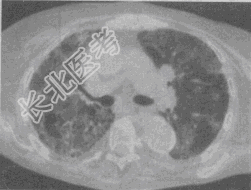

- 单项选择题患者,女, 45岁,气急, 咳嗽,胸痛, 手、足关节痛,关节肿胀, 结合CT图像,最可能的诊断是

A、肺癌

B、特发性肺间质纤维化

C、系统性红斑狼疮

D、硬皮病

E、类风湿肺病